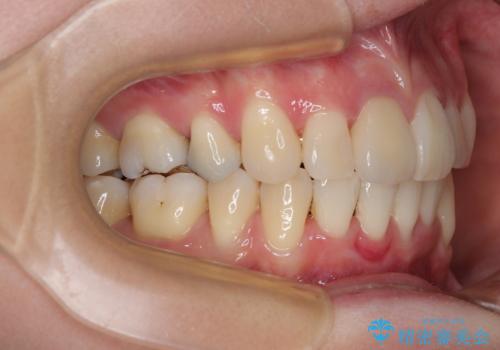

- 八重歯と上の前歯が出っ歯になっていることを気にして来院された患者様です。

横から見た際の口元の飛び出した印象も改善したいとのことで、上下左右の第一小臼歯4本を抜歯し、ワイヤー装置にて抜歯矯正を行うこととしました。

前歯の変色している歯は、神経組織が壊死していたため、矯正治療前に根管治療を実施し、矯正治療後にオールセラミッククラウンにて補綴治療を行うこととしました。